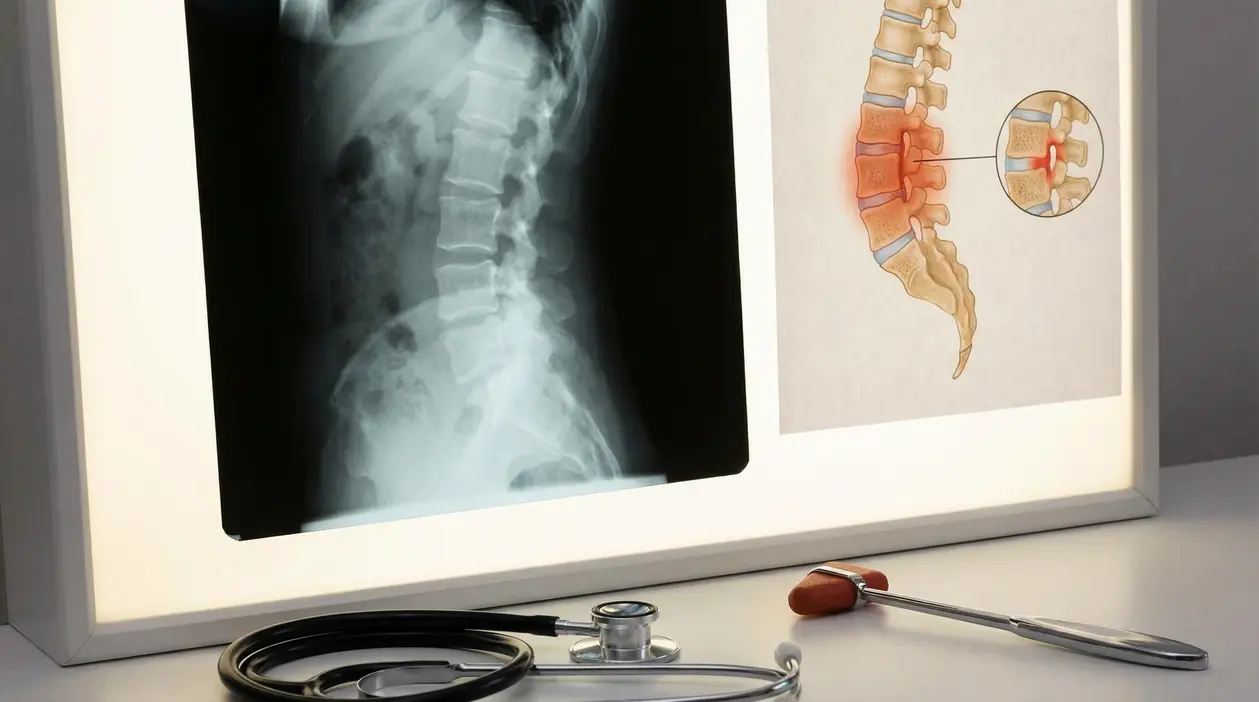

La diagnosi non si basa su un solo esame, ma sull’insieme di sintomi, visita specialistica e immagini. Il riferimento è il reumatologo, che valuta il quadro clinico e decide quali approfondimenti servono.

Gli strumenti più usati sono:

- radiografie, utili per vedere la sacroileite, cioè l’infiammazione delle articolazioni sacroiliache

- risonanza magnetica, spesso capace di evidenziare segni precoci prima delle alterazioni radiografiche